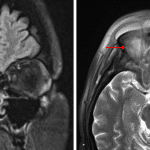

- Extensive surrounding right greater than left frontal scalp and right periorbital edema and soft tissue enhancement

- Mild infiltrative T2/FLAIR signal hyperintensity in the superior extraconal right orbit without discrete collection. Associated right proptosis

- Mild mucosal thickening of right ethmoid air cells

- Frontal sinusitis with epidural abscess and subgaleal abscess

Right frontal sinusitis complicated by extension through the inner and outer tables with a contiguous right frontal subgaleal abscess and small epidural abscess. Surrounding right greater than left frontal scalp and right periorbital cellulitis. Postseptal right orbital cellulitis involving the superior extraconal orbit with associated right proptosis but no discrete intraorbital abscess. No evidence of cerebritis or brain abscess.